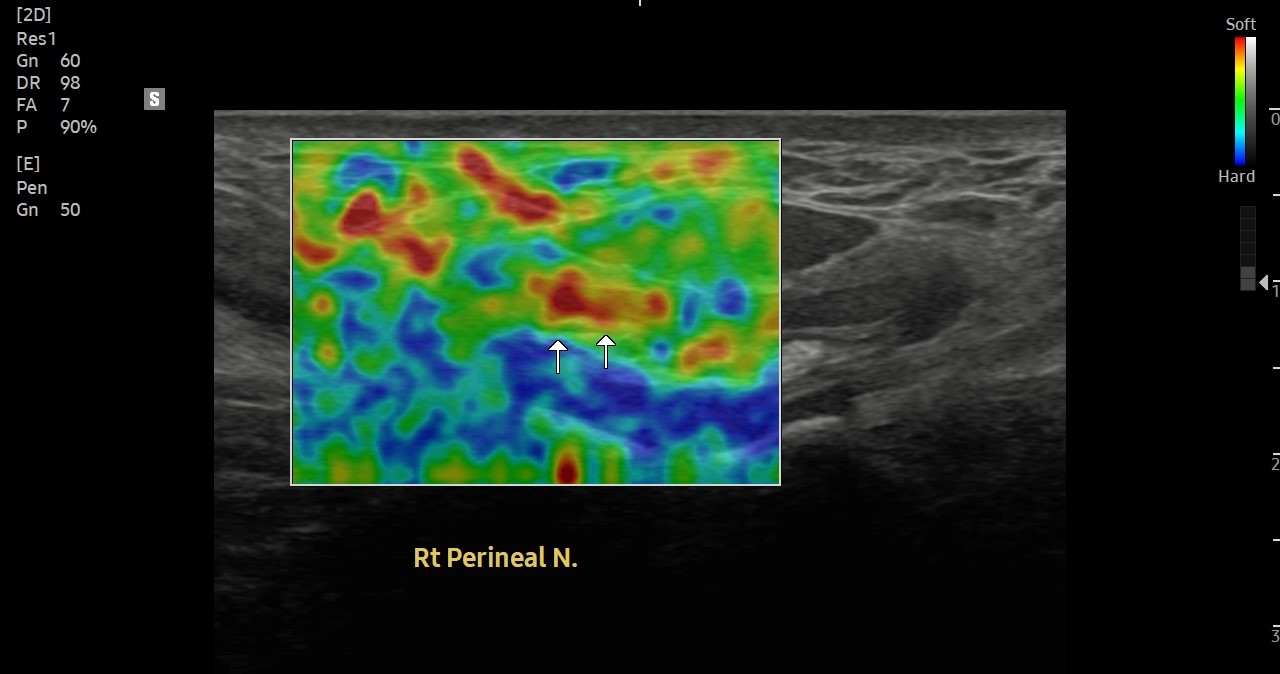

[치료 전]

[치료 후]

- 치료횟수 : 30 회